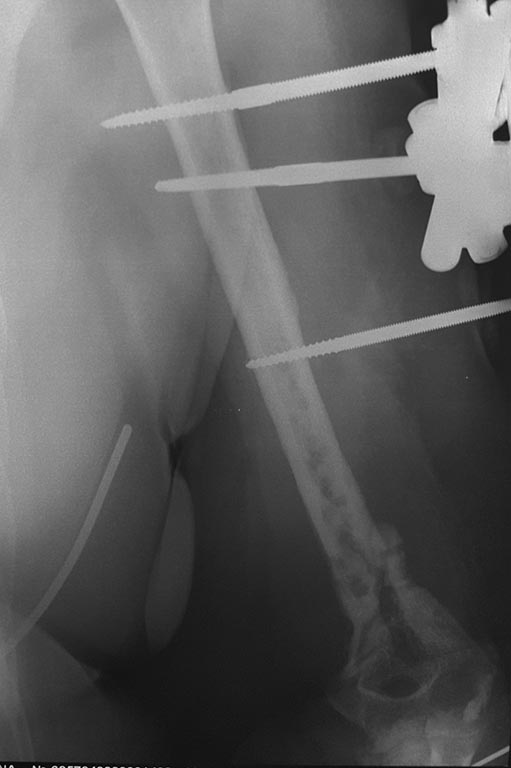

Уважаемые коллеги! Помогите с тактикой дальнейшего лечения пациентки Д

56 лет: февраль 2015 закрытый многооскольчатый перелом левого плеча в

дистальной трети, остеосинтез пластиной с ОК - через 2 недели вырваны

дистальные винты, повторный остеосинтез пластиной с угловой

стабильностью через 1 месяц вырваны винты, угроза инфицирования

гематомы, удаление пластины, спице стержневой АВФ. заживление первичное,

последний месяц без свищей и отделяемого.